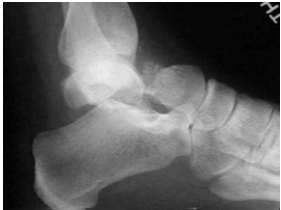

59 下圖為何種骨折?

(A) calcaneus fracture(B) talus fracture(C) navicular fracture(D) cuboid fracture